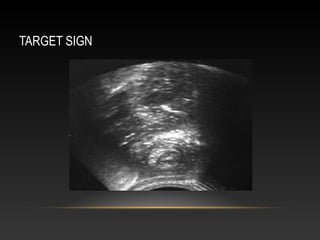

2-ULTRASOUND

•Used to diagnose IS and prevent unnecessary enemas

High sensitivity and specificity

No radiation exposure

Exclude other pathologies.

•Findings:

-target sign (transverse)

-sandwich sign (longitudinal)

TARGET SIGN

Central hyperechoic region (C) surrounded by hypoechoic and

homogeneous edge (bowel wall)